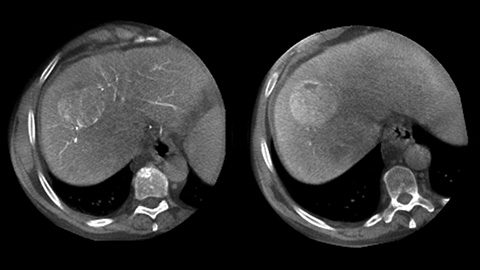

By opening the arc to the left of the patient, CBCT allows off center positioning of the patient table and therefore better centering of the FOV. It significantly increases image coverage to help visualize tumors on the periphery of the organ [2].

CBCT enables 3D acquisition of an arterial phase to visualize vascular structures and a post-arterial (delayed phase) to optimally visualize accumulation of contrast medium, in a single automatic step [3].

Dual View allows simultaneous visualization of two CBCT datasets (pre and post). Both arterial and delayed phase can be displayed next to each other or in a single fused overlay view.